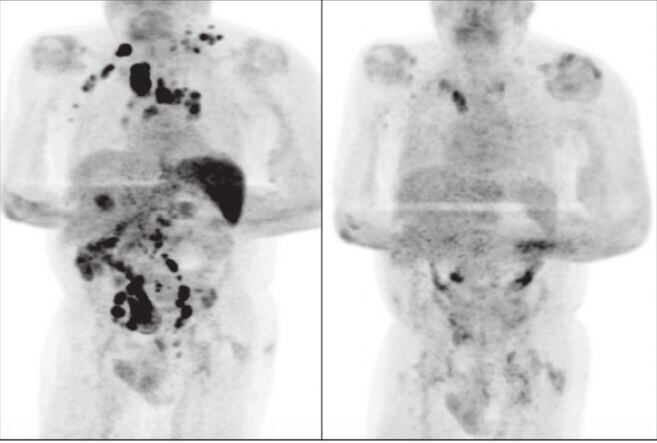

Los especialistas Sarah Challenor y David Tucker, declararon a la British Journal of Haemathology, que el paciente de 61 años había sido diagnosticado con cáncer por linfoma de Hodgkin en etapa 3, es decir, la enfermedad ya estaba en todo su cuerpo; sufría de graves bajas de peso, inflamación de los ganglios, y de problemas renales que trataba con diálisis.

Cuatro meses después, el paciente regresó al hospital a una consulta médica de rutina. Para sorpresa de sus doctores, el hombre mostró una mejoría evidente ante el cáncer: ya no estaban inflamados los ganglios.